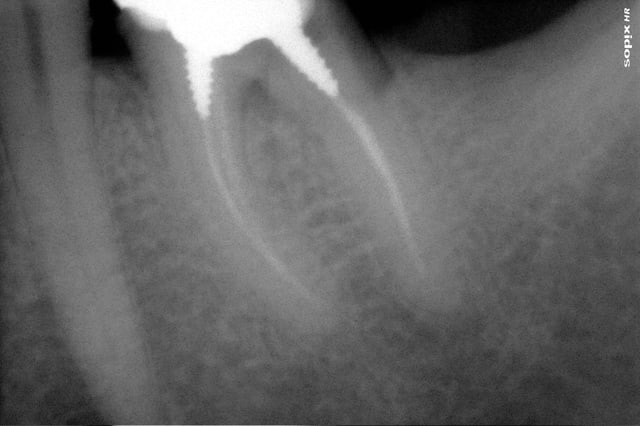

voici la radio pré-op de 36(couronne de plus de 10 ans),il semble qu il y est une fracture du plancher en rapport avec le screw post distal;

46 a du etre extraite pour la meme raison il y a 4 ans.

Le patient revient pour refection préventive 36 assymptomatique,(n'a pas les moyen de faire un implant)

Mais est-ce réellment une perforation? à la radio on dirait plutot une fracture complete de la racine distale.

La 37 est absente...l'occlusion est concentrée sur une seule molaire , pas très solide...poche au distal ? perte osseuse ?

Je trouve que l'idée de l'hémisection plutôt risquée...pas de dent au distal...occlusion compromise